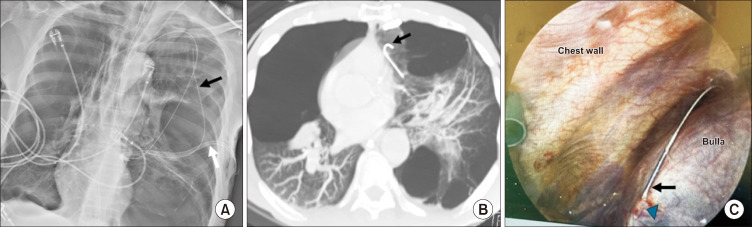

在Seldinger技术中,导丝缺失的发生率很低,但可能由于操作错误而发生。报道的发生率各不相同,中心静脉置管和其他血管通路手术的发生率从0.1%到0.8%不等。我们报告一例罕见的病例,在呼吸机诱发的气胸患者的Seldinger-based胸管插入后,导丝在肺大球内保留。由于长时间的空气泄漏,导丝被移除,并通过电视胸腔镜对受影响的肺实质进行楔形切除,同时进行滑石粉胸膜切除术。使用Seldinger技术的闭式开胸术需要在接受机械通气的肺气肿患者中谨慎进行。为了便于肺部收缩,并尽量减少针和导丝放置期间肺损伤的风险,气管内管可暂时与呼吸机断开。应避免过度插入导线和扩张器。监督和模拟训练对于防止这类“永远不会发生的事件”至关重要。

The incidence of a missing guidewire during the Seldinger technique is low but can occur due to procedural errors. Reported rates vary, ranging from 0.1% to 0.8% in central venous catheterization and other vascular access procedures. We present a rare case of a retained guidewire within a pulmonary bulla following Seldinger-based chest tube insertion in a patient with ventilator-induced pneumothorax. Due to a prolonged air leak, the guidewire was removed, and wedge resection of the affected lung parenchyma, along with talc pleurodesis, was performed via video-assisted thoracoscopy. Closed thoracostomy using the Seldinger technique requires caution in emphysematous patients receiving mechanical ventilation. To facilitate lung deflation and minimize the risk of lung injury during needle and guidewire placement, the endotracheal tube can be temporarily disconnected from the ventilator. Over-insertion of the wire and dilator should be avoided. Supervision and simulation training are crucial to prevent this type of "never event."